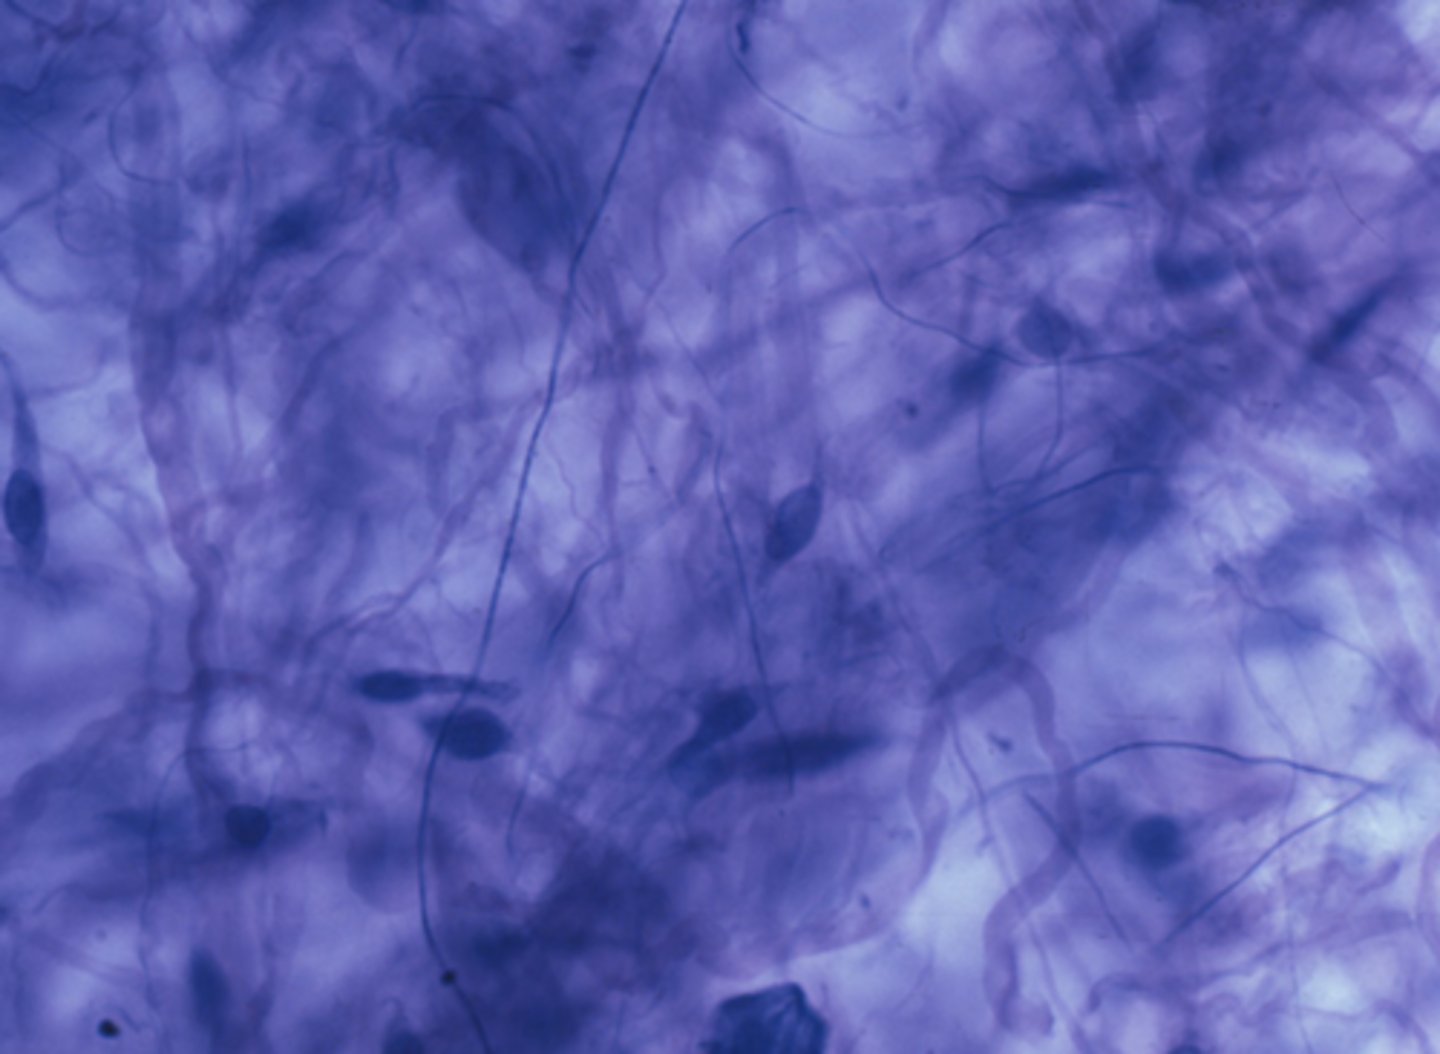

connective tissue

Which of the four major tissue types is presented in the following image of the mesentery? (Hint: just answer one of the four major tissue types here, we don't need subtypes)

Cells produce an extracellular matrix

Which is a characteristic of the tissue type in the previous image: Connective Tissue